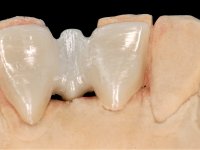

In the dental lab, a Maryland bridge with a zirconia framework veneered with a feldspathic ceramic was built. The wings internal surface also had a very thin coating of a zirconia adhesive to allow its bonding to the abutments enamel. This Maryland bridge tried to join the mechanical strength of the framework, to the bonding of the ceramic to the enamel, and to the aesthetics’ of the zirconia’s veneering with a feldspathic ceramic.

Then, this Maryland bridge was bonded to the abutments.